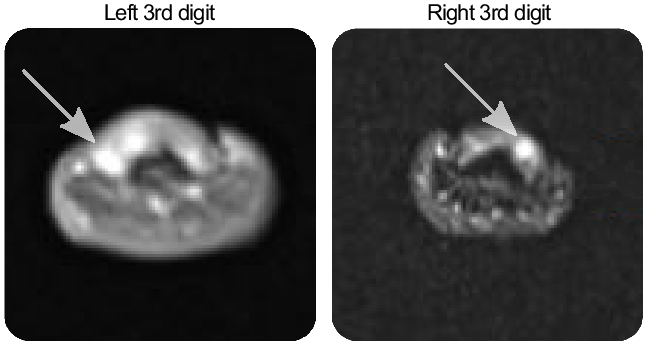

He began having episodes of fingertip pain 6 years prior to presentation to our clinic. Each episode lasted 5–10 minutes and could include one or several fingers. These pain crises were rated up to 9/10 in severity. Triggers included touch, cold, heat, or pressure. Over the course of 5 years, he had multiple surgical resections of the subungual lesions providing partial relief of pain. Five of the six resected lesions were glomus tumors, and one was a neurofibroma. He tried several medications for the pain including naproxen, gabapentin, and topical ketamine which were not helpful. On examination, he had no visible abnormalities of his fingertips, even with trans-illumination. There was no tenderness to palpation. A left-hand MRI showed a subungual lesion consistent with glomangioma in the 3rd digit and post-operative changes in the 4th digit. (Figure 1, left panel). In the right hand, there were lesions consistent with glomangioma in the 1st, 3rd, and 4th digits (Figure 1, right panel).

Figure 1: Glomangioma (arrows) are visible on axial hand MRI scans.

Figure 2: Coronal T1-weighted post-gadolinium MRI of the hands showing small, enhancing glomangiomas, best seen on the right distal 3rd digit (arrow) and on the left 3rd digit (arrow), better seen on axial images. The associated pain scores and durations for each digit are shown in the adjacent graph. The patient recorded his pain crises before and after starting trametinib. Day 0 represents the first day taking trametinib 2 mg daily.